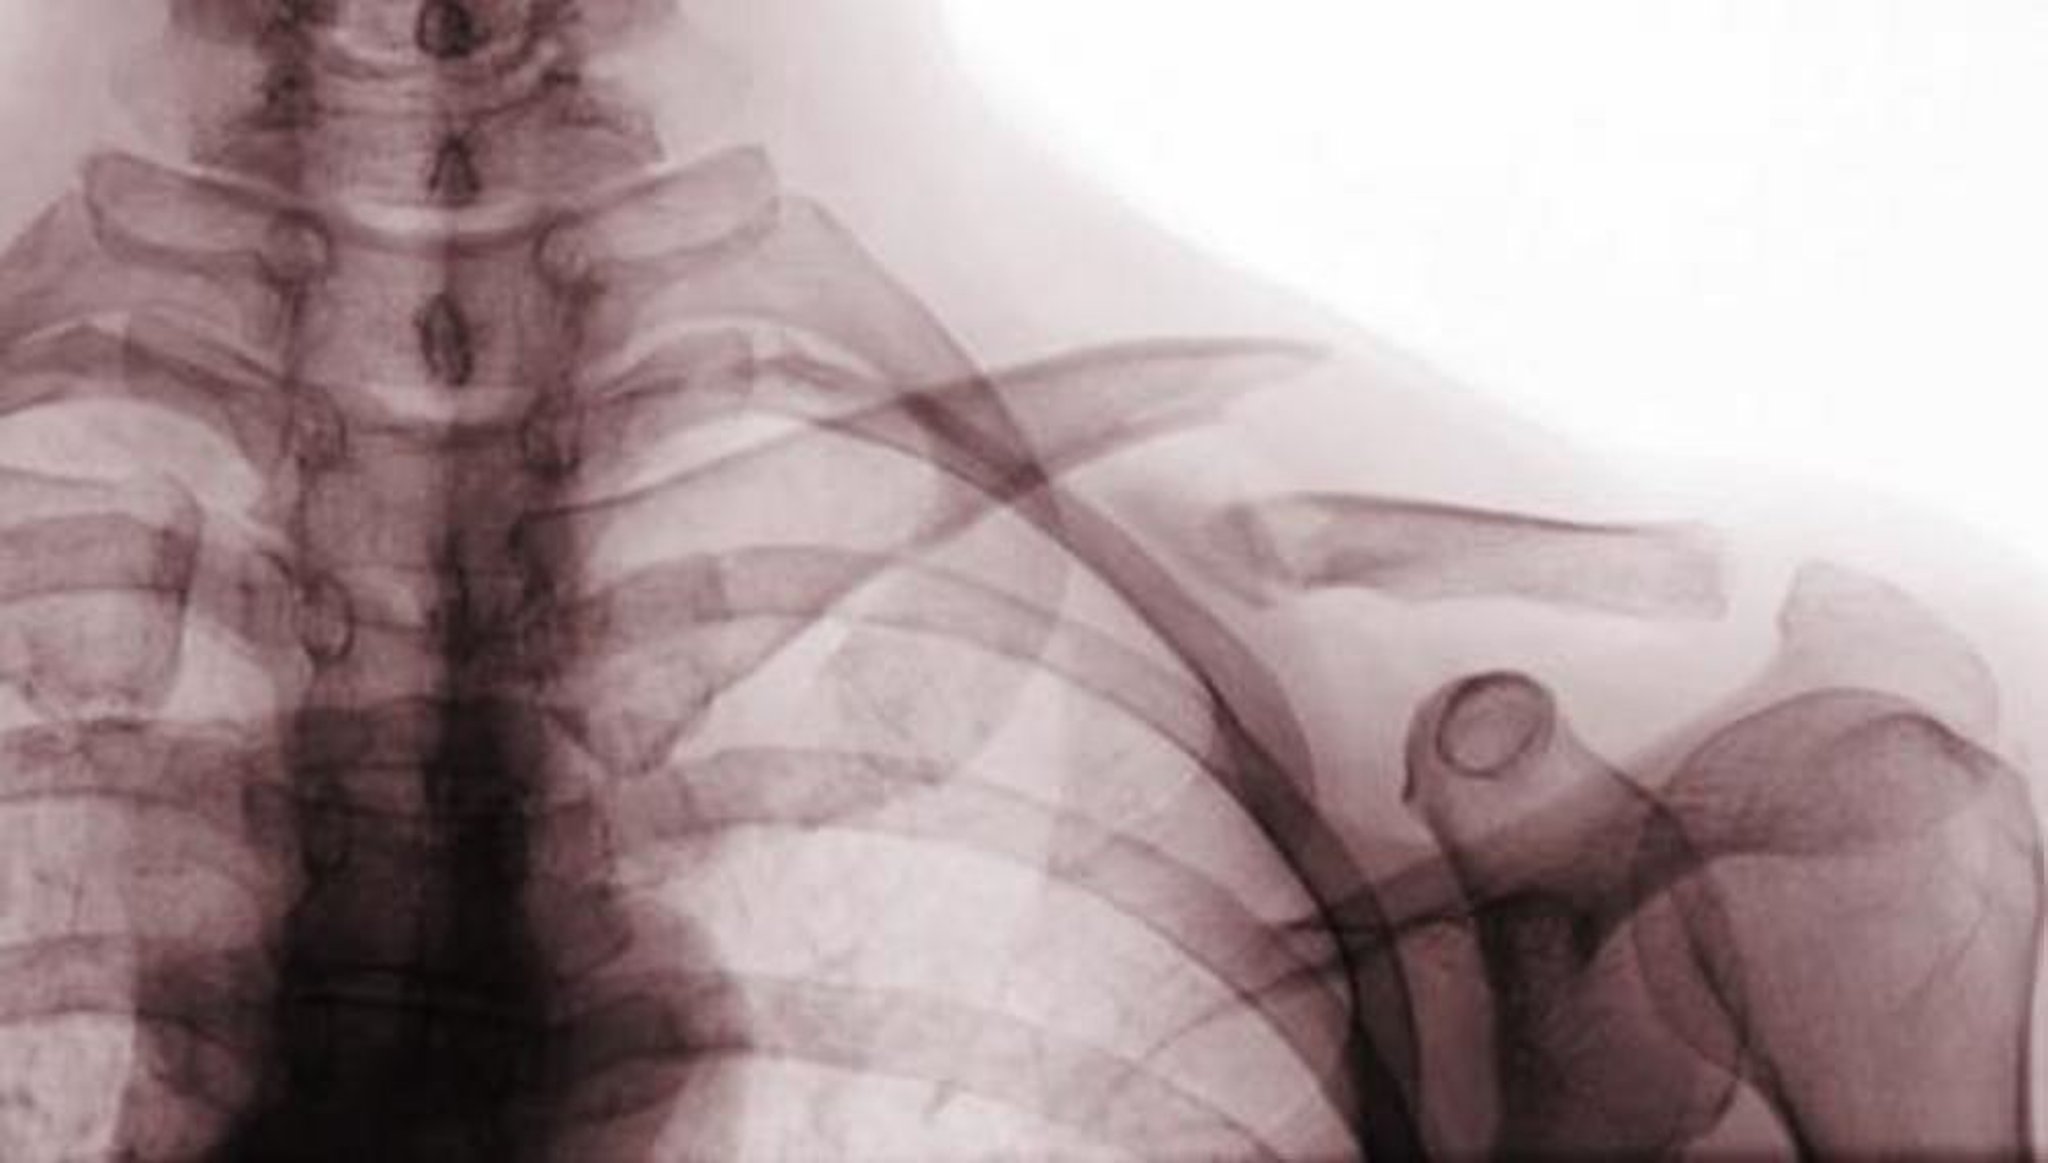

Перелом ключицы

Этот переднезадний рентгеновский снимок показывает смещенный перелом средней трети ключицы (перелом класса A).

Scott Camazine/SCIENCE PHOTO LIBRARY